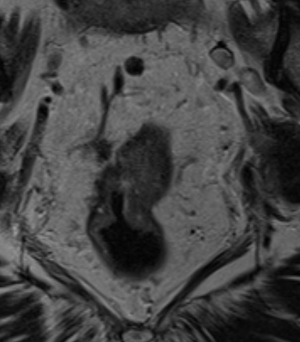

МР-диагностика рака тела матки

МР-диагностика рака шейки матки

МР-диагностика рака яичников

МР-диагностика рака предстательной железы (мультипараметрическая МРТ)

МР-диагностика рака прямой кишки